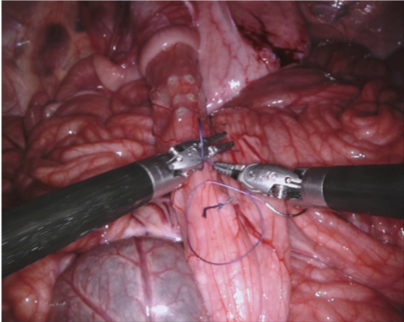

In 2017 we organized a follow-up challenge222https://endovissub2017-roboticinstrumentsegmentation.grand-challenge.org where a team at Intuitive Surgical manually segmented images from porcine robot assisted nephrectomy procedures. We aimed to improve on the previous challenge by first increasing the label quality by using hand-created labels rather than automatic labelling, secondly by adding greater variance in the background by using 10 separate procedures and finally by providing more type and part labels for the instruments.

Our challenge was made up of 3 sub-problems. The first was binary instrument segmentation, where each frame was separated into da Vinci Xi instruments and a background class, which contained an ultrasound probe, surgical clips and porcine tissues. The second task was instrument part segmentation, where we scored the participants on whether they could correctly segment each articulating part of the instrument (see Fig. 3). Our final task was to segment and classify the instruments (see Fig. 4).

We provided the first 225 frames of 8 sequences as training data and kept the last 75 frames of those 8 sequences as test data. 2 of the full 300 frame sequences were kept as test sequences. Test labels were kept hidden from the participants. Our datasets contain 7 different robotic surgical instruments. The Large Needle Driver, Prograsp Forceps, Monopolar Curved Scissors, Cadiere Forceps, Bipolar Forceps, Vessel Sealer and additionally a drop-in ultrasound probe, which is typically held in the jaws of the Prograsp Forceps instrument. Samples from the training datasets are depicted in Fig. 2 and examples of the different instrument types are shown in Figure 3 and 4.